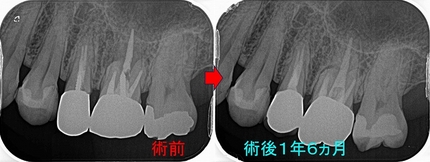

レントゲン

2026 EEdental MIH (1).jpg

かなり大きな虫歯があります。

2026 EEdental MIH (2).jpg

特殊な削り方をしてレジン(プラスチック)を詰めました。

親知らずの影響か、セメント質の肥厚が見られました。

一般的な治療はこんな感じで

2026 EEdental MA.jpg

大きく削って神経取っても、見えない為に虫歯は残したまま・・・

ホントこの部位の虫歯の治療は知っている・知っていないで大きく差が出てしまいます(>。<)